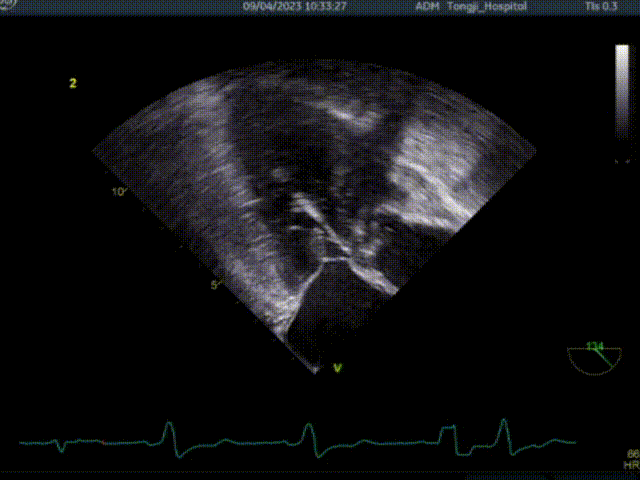

术前超声TEE检查结论:

1. 左室非对称性肥厚,左室流出道梗阻,二尖瓣重度关团不全;

2. 二尖期后叶脱垂;

3. 卵圆孔未闭(极细缝隙)。

患者术前大量反流,前叶SAM征,室间隔增厚最厚处13mm